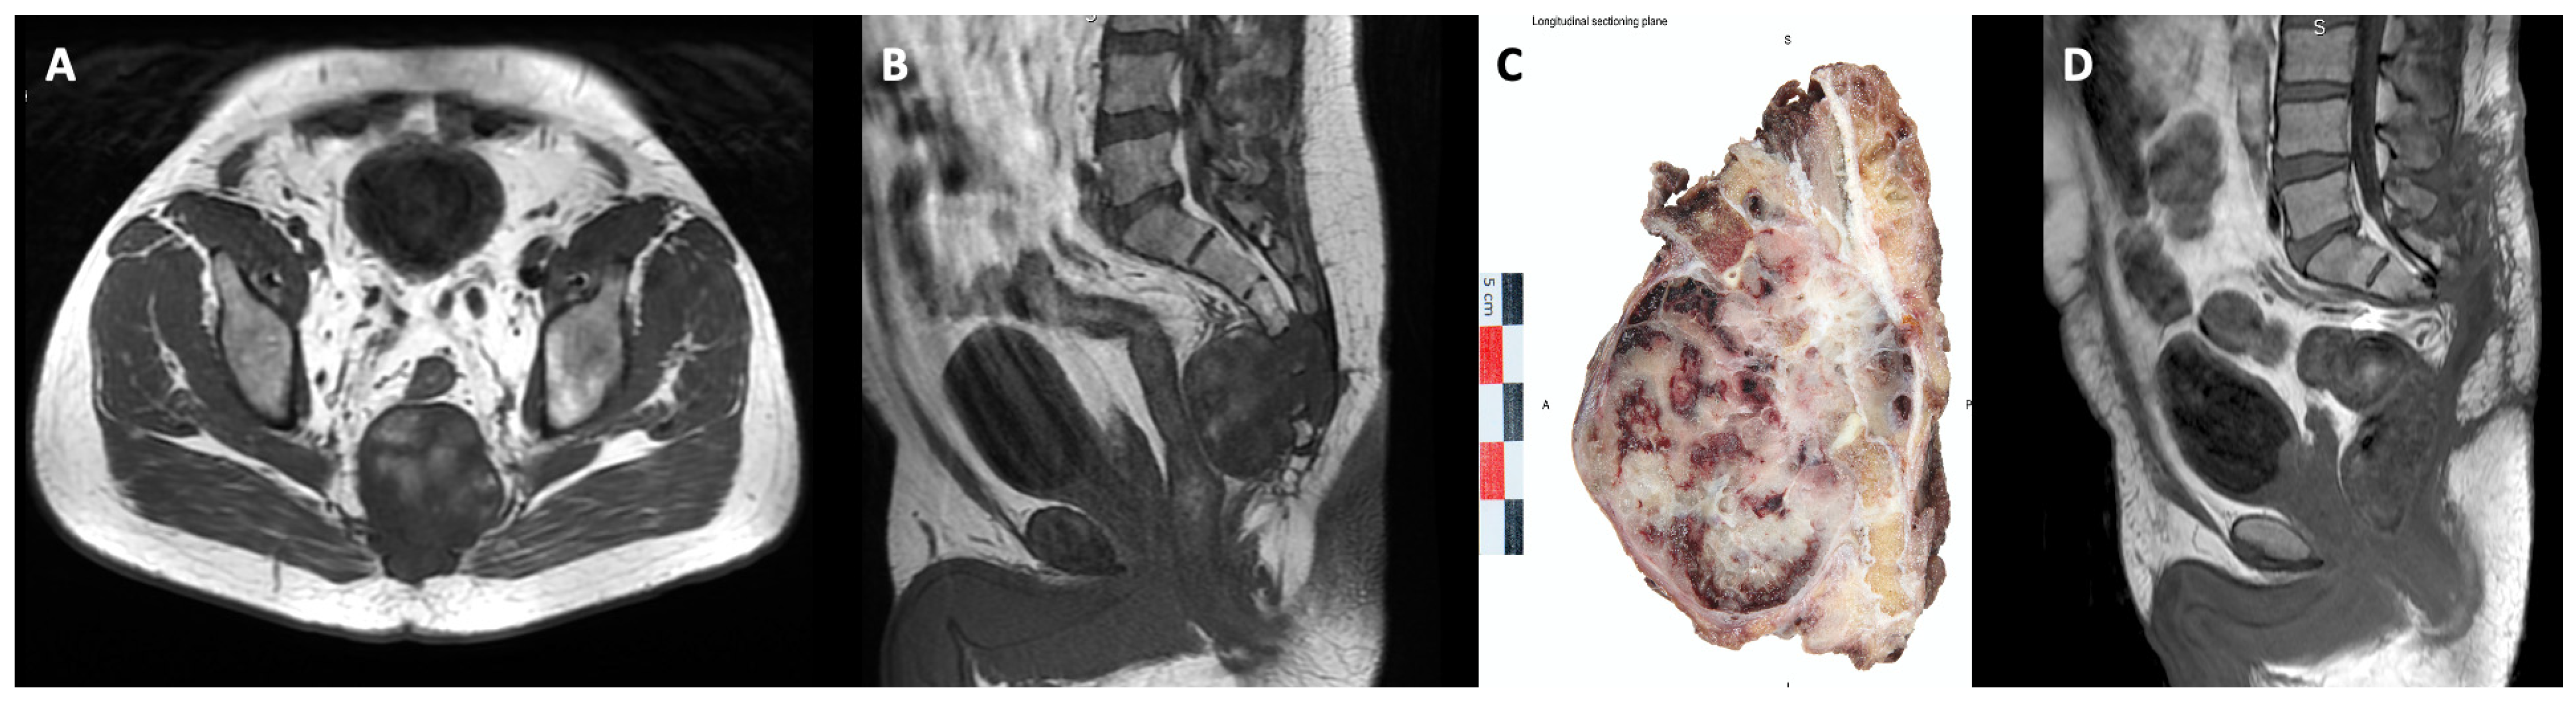

A combined anterior and posterior approach was performed in 14/27 patients (51.9%), whereas only a midline posterior approach was performed for the remaining 48.1% based on the most cephalad extent of the tumor (Figure 1).

Figure 1.

(A,B): T1-weighted axial and sagittal MRI of an S3 level sacral chordoma (male, 55 year), (C) post-en-bloc resection specimen (sagittal midline view), (D) postoperative progression-free MRI evaluation at 6 months after tumor resection surgery (contrast-enhanced T1-weighted sagittal view).